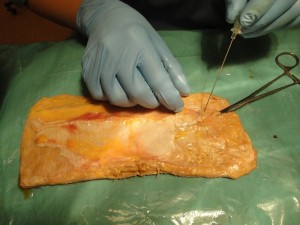

Особенности зоны, кровоснабжаемой из перфорирующей ветви малоберцовой артерии исследовались нами посредством проведения рентгенангиографии на патоморфологическом материале. Были исследованы 16 препаратов лоскутов. Учитывая территорию кровоснабжения исследуемой ангиосомы, которая составляет максимально до 18 см в длину и до 9 см в ширину, кожно-фасциальный лоскут препарировался в несколько больших границах (+ 3 см в длину и ширину), но не выходя за пределы гребня большеберцовой кости [4]. Выделенная перфорантная ветвь малоберцовой артерии зондировалась канюлей на глубину 2-4 см, при затруднении проведения канюли, её проводили по металлическому проводнику 0.014 inch. После этого на артерию поверх канюли накладывался турникет, и герметизировали сосуды по периферии лоскута путем наложения лигатур или методом электрокоагуляции (рис. 2). В ходе подготовки сосудов к контрастированию они промывались раствором гепарина (5 000 Ед / 100 мл). Сосудистое русло заполнялось под давлением йод содержащим контрастным веществом (Ультравист – 370; Визипак – 320), производились рентгенангиографические снимки в нескольких фазах наполнения. С целью определения размеров зоны с устойчивым кровоснабжением от перфорантной артерии (ангиосомы) и её индивидуальной вариабельности, проводили планиметрическое исследование с определением возможных размеров формирования лоскута (рис. 3).

Рис. 2 А. Выделение перфорантной артерии и взятие патоморфологического материала (кожно-фасциального лоскута); Б. Препарат с зондированной перфорантной артерией и проведенной герметизацией.